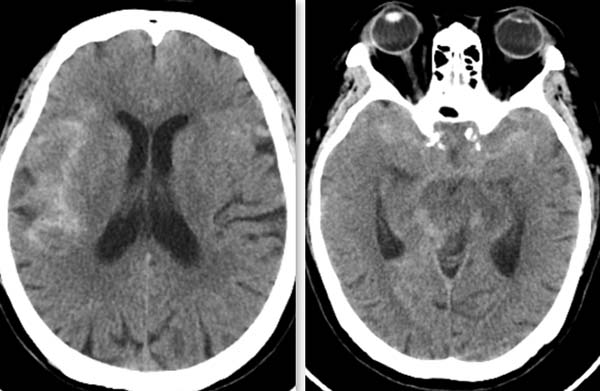

今年已是“米寿之年”的患者李女士有30余年高血压和8年冠心病史,平素生活可自理。入院前3天突发剧烈头痛,伴恶心,未及时就医诊治。9月1日清晨,她突发头痛并加重,前往清华大学附属垂杨柳医院急诊就诊,头颅CT提示蛛网膜下腔出血。请神经外科会诊并进行了科内专家组讨论,结合头颈动脉CTA检查,认为李女士为颅内动脉瘤破裂伴蛛网膜下腔出血。

▲头颅CT显示蛛网膜下腔出血,右侧偏多